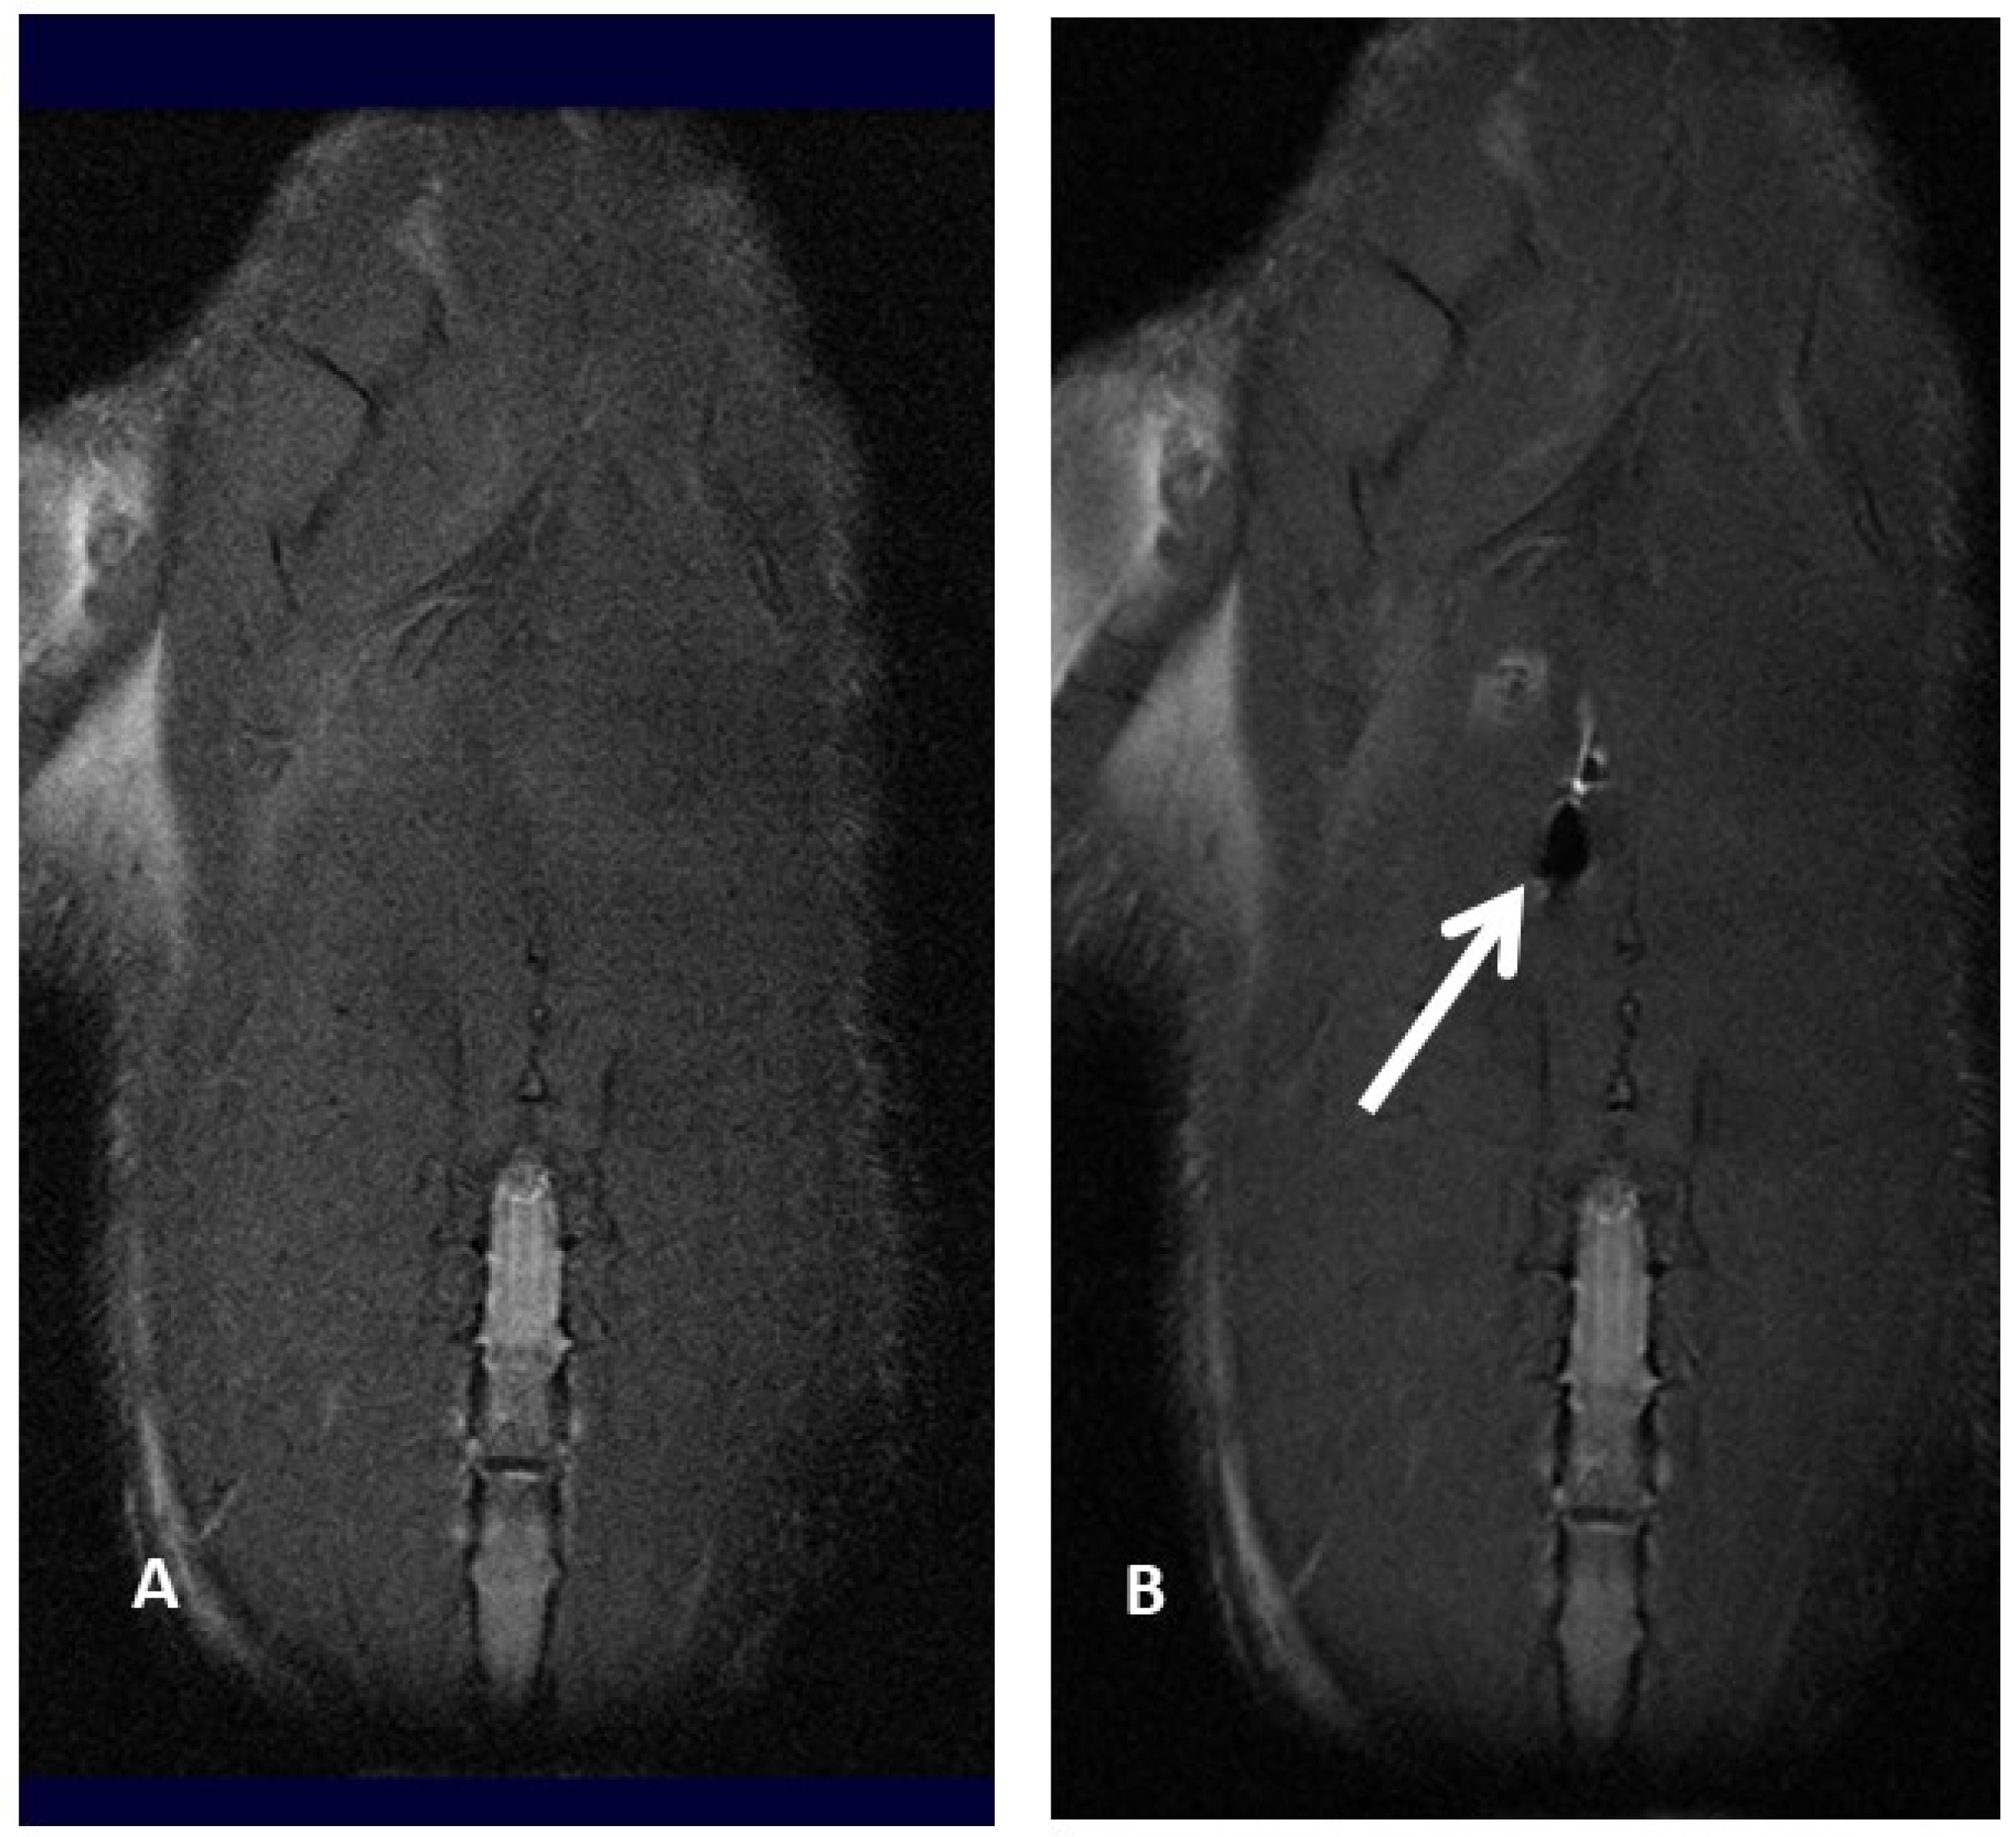

3. Imaging

Molecular imaging provides a better knowledge of cell fate after transplantation, thus optimizing cell therapy results. In fact, it has already been reported that after systemic injection, MSC amass in the lung and vascular beds of other organs and tissues, thus reducing the number of MSC moving to the target site for therapy [26,27]. Positron emission tomography (PET), magnetic resonance imaging (MRI), single-photon emission computed tomography (SPECT), bioluminescence imaging (BLI) and fluorescence imaging (FLI) are several imaging techniques able to visualize signals produced by labeled MSC, thus making it possible to properly track MSC, revealing cell fate, migration and implant after transplantation. Molecular imaging plays a pivotal role in determining the appropriate cell type, transfer technique, cell dosage, and treatment window, as well as in evaluating potential toxic side effects by identifying early cell graft modification into neoplasms, which cannot be detected in a timely manner by standard imaging technique. In addition, molecular imaging of MSC provides useful information about cell survival, proliferation and differentiation within the target area: these data make it possible to optimize the therapeutic dose–response curve, identifying the best dosage and dosing frequency of cell therapy [28,29,30,31,32,33]. To date, imaging and tracking of transplanted MSC have not yet been definitely assessed, and several issues related to MSC migration and engraftment to extra-target sites need to be further assessed before molecular imaging techniques can be safely applied to daily clinical practice. For example, Scharf et coll. have demonstrated that when performing ultrasound-guided MSC intralesional injection for tendonitis, only a few cells remain within collagenous tendon while, on the contrary, many cells scatter to the surrounding fascia, disclosing an MSC greater delocalization than expected [34]. Similarly, extracellular vesicles (EV)—which are paracrine mediators released by MSC under specific conditions, disclosing potential application in cell-based therapies—tend to preferentially migrate to the lung, spleen and liver after systemic administration [35,36,37,38,39,40]. Cellular imaging techniques are not invasive and provide high-resolution images, thus resulting in very important to defining the cell fate after implantation; in experienced hands, they are relatively easy to use, although not widely available (e.g., 8-Tesla MRI for small animals) because of their exclusive use for scientific non-clinical purposes (Figure 2A,B).

Magnetic resonance imaging offers high-resolution images that range from 50 μm in experimental animal models to 300 μm in clinical settings; since it does not rely on ionizing radiations, it is one of the less invasive methods of tracking MSC “in vivo”. However, MSC have to be pre-labeled by some contrast media: among them, there are some positive contrast media, like gadolinium, and some negative contrast media, such as superparamagnetic iron-oxide (SPIO) and ultrasmall superparamagnetic iron-oxide (USPIO), which make it possible to identify and track transplanted MSC within the target environment. Another more recent approach for MSC detection by MRI is MSC labeling by perfluorocarbon (PFC) nanoemulsions, requiring dedicated 19Fluorine MRI. In our personal experience, we compared magnetic resonance imaging of iron-labeled cells and magnetic resonance spectroscopy of fluorine-labeled cells. We explored whether rat bone marrow MSC can be effectively labeled with superparamagnetic iron-oxide (SPIO) nanoparticles and perfluorocarbon (PFC) nanoemulsion formulations without interfering with cell viability and matched magnetic resonance imaging (MRI) and magnetic resonance spectroscopy (MRS) findings from iron-labeled and fluorine-labeled MSC. The SPIO negative contrast enhancement provides an excellent view even in the case of very small numbers of labeled cells but can be easily confused with other sources of magnetic sensitivity effects, like blood vessels or air bleeds, in relation to the anatomical site under evaluation. As prospective clinical applications might include lung tissue evaluation for MSC injection in the repair process and assessing MSC migration and engraftment into the lungs, we also labeled cells with PFC nanoemulsions, which can be identified by 19F MRI. Our finding suggested that both types of contrast agents (PFC and SPIO) can be successfully used for MSC labeling, although further studies were needed to upgrade the efficacy of PFC labeling [47]. In particular, we referred to our previous experience of bronchopleurla fistula (BPF) repair after bronchial disruption following major anatomical lung resection for cancer.

Subsequently, in fact, we investigated the role of 7-Tesla magnetic resonance imaging to track MSC labeled by perfluorocarbon (PFMSC): PFC-based emulsion provided better views in an “in-vivo” rat model compared with USPIO contrast medium, particularly when assessing lung tissue. MSC diffusion to other solid organs, in this case only to the liver, was also better disclosed by PFC-labeled MSC, probably due to the iron content within the liver. A linear decline of delivered PFC-labeled MSC was reported 24 and 48 h after the injection in lung tissue; in nearly half of the observations, PFC-labeled MSC seeding to the liver was reported, with a similar decline over time as observed in the lung. We might argue that MSC locally injected into the lung might scatter to the liver through the blood flow of the cardiac cycle. Nevertheless, considering that about 40% of the rats did not disclose any signal in the liver at time zero, it might be argued that cell migration to the liver only happened when MSC were injected more centrally and thus closer to pulmonary vessels, whereas MSC injected more peripherally in the lung parenchyma were not able to reach the systemic blood flow [50,51].

Figure 2. Magnetic resonance imaging of a rat before (A) and after (B) injection of ferumoxides labeled mesenchymal stromal cell, resulting in an apparent loss of signal (white arrow and black hole).